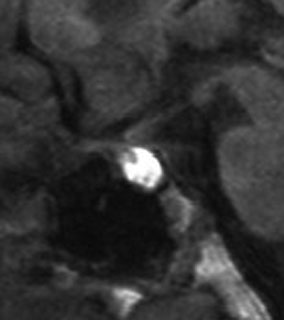

尿崩症で発症した小さな腫瘍

尿崩症で発症した9歳男児にみられたxanthogranuloma of the sellar resion。左はT1強調画像で高信号,右はT2強調画像で低信号であり,肉芽腫の特徴がみられます。のう胞部分はT2強調画像で,高信号になります(右図)。このような小さな頭蓋咽頭腫やラトケのう胞が尿崩症を呈することはまれですが,黄色肉芽腫の場合は小さくても症候性となることが多いです。神経下垂体組織が炎症性に破壊されるからと考えられます。